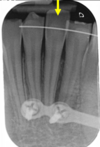

is the following periapical pathology or not?

yes - it is crowned - apical radiolucency - lamina dura tracking off